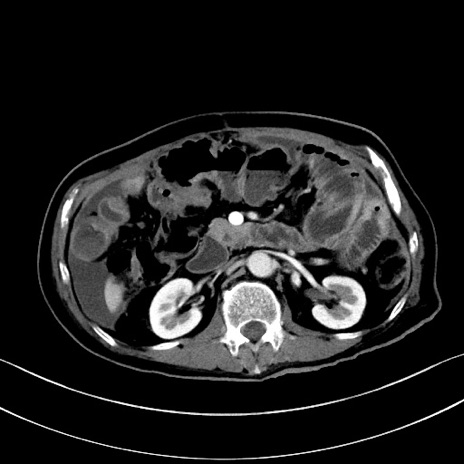

症例28(横断像)

【症例】60歳代男性

【主訴】嘔吐

【現病歴】胃癌にて胃全摘後。食思不振が悪化し、夜中に嘔吐することがある。

【既往歴】胃癌、胃全摘、脾摘、胆摘後

【データ】WBC 5900、CRP 10.56